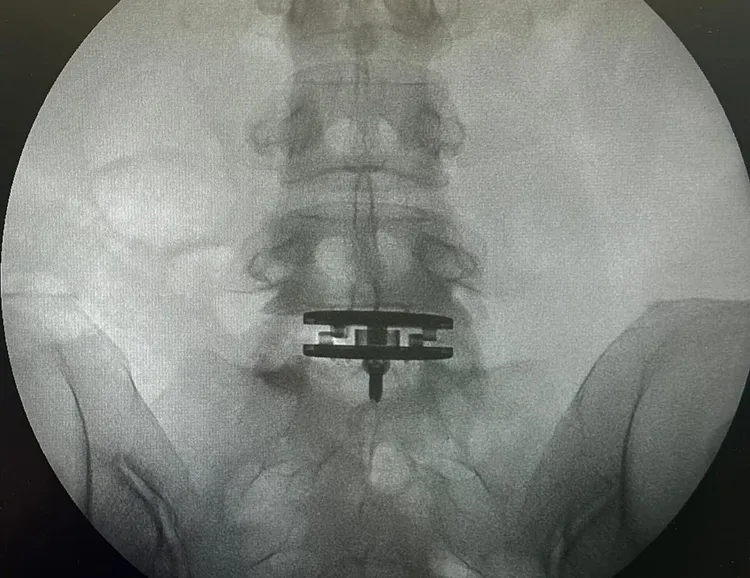

徐濠縈換了人工椎間盤。翻攝hilaryxtsui IG